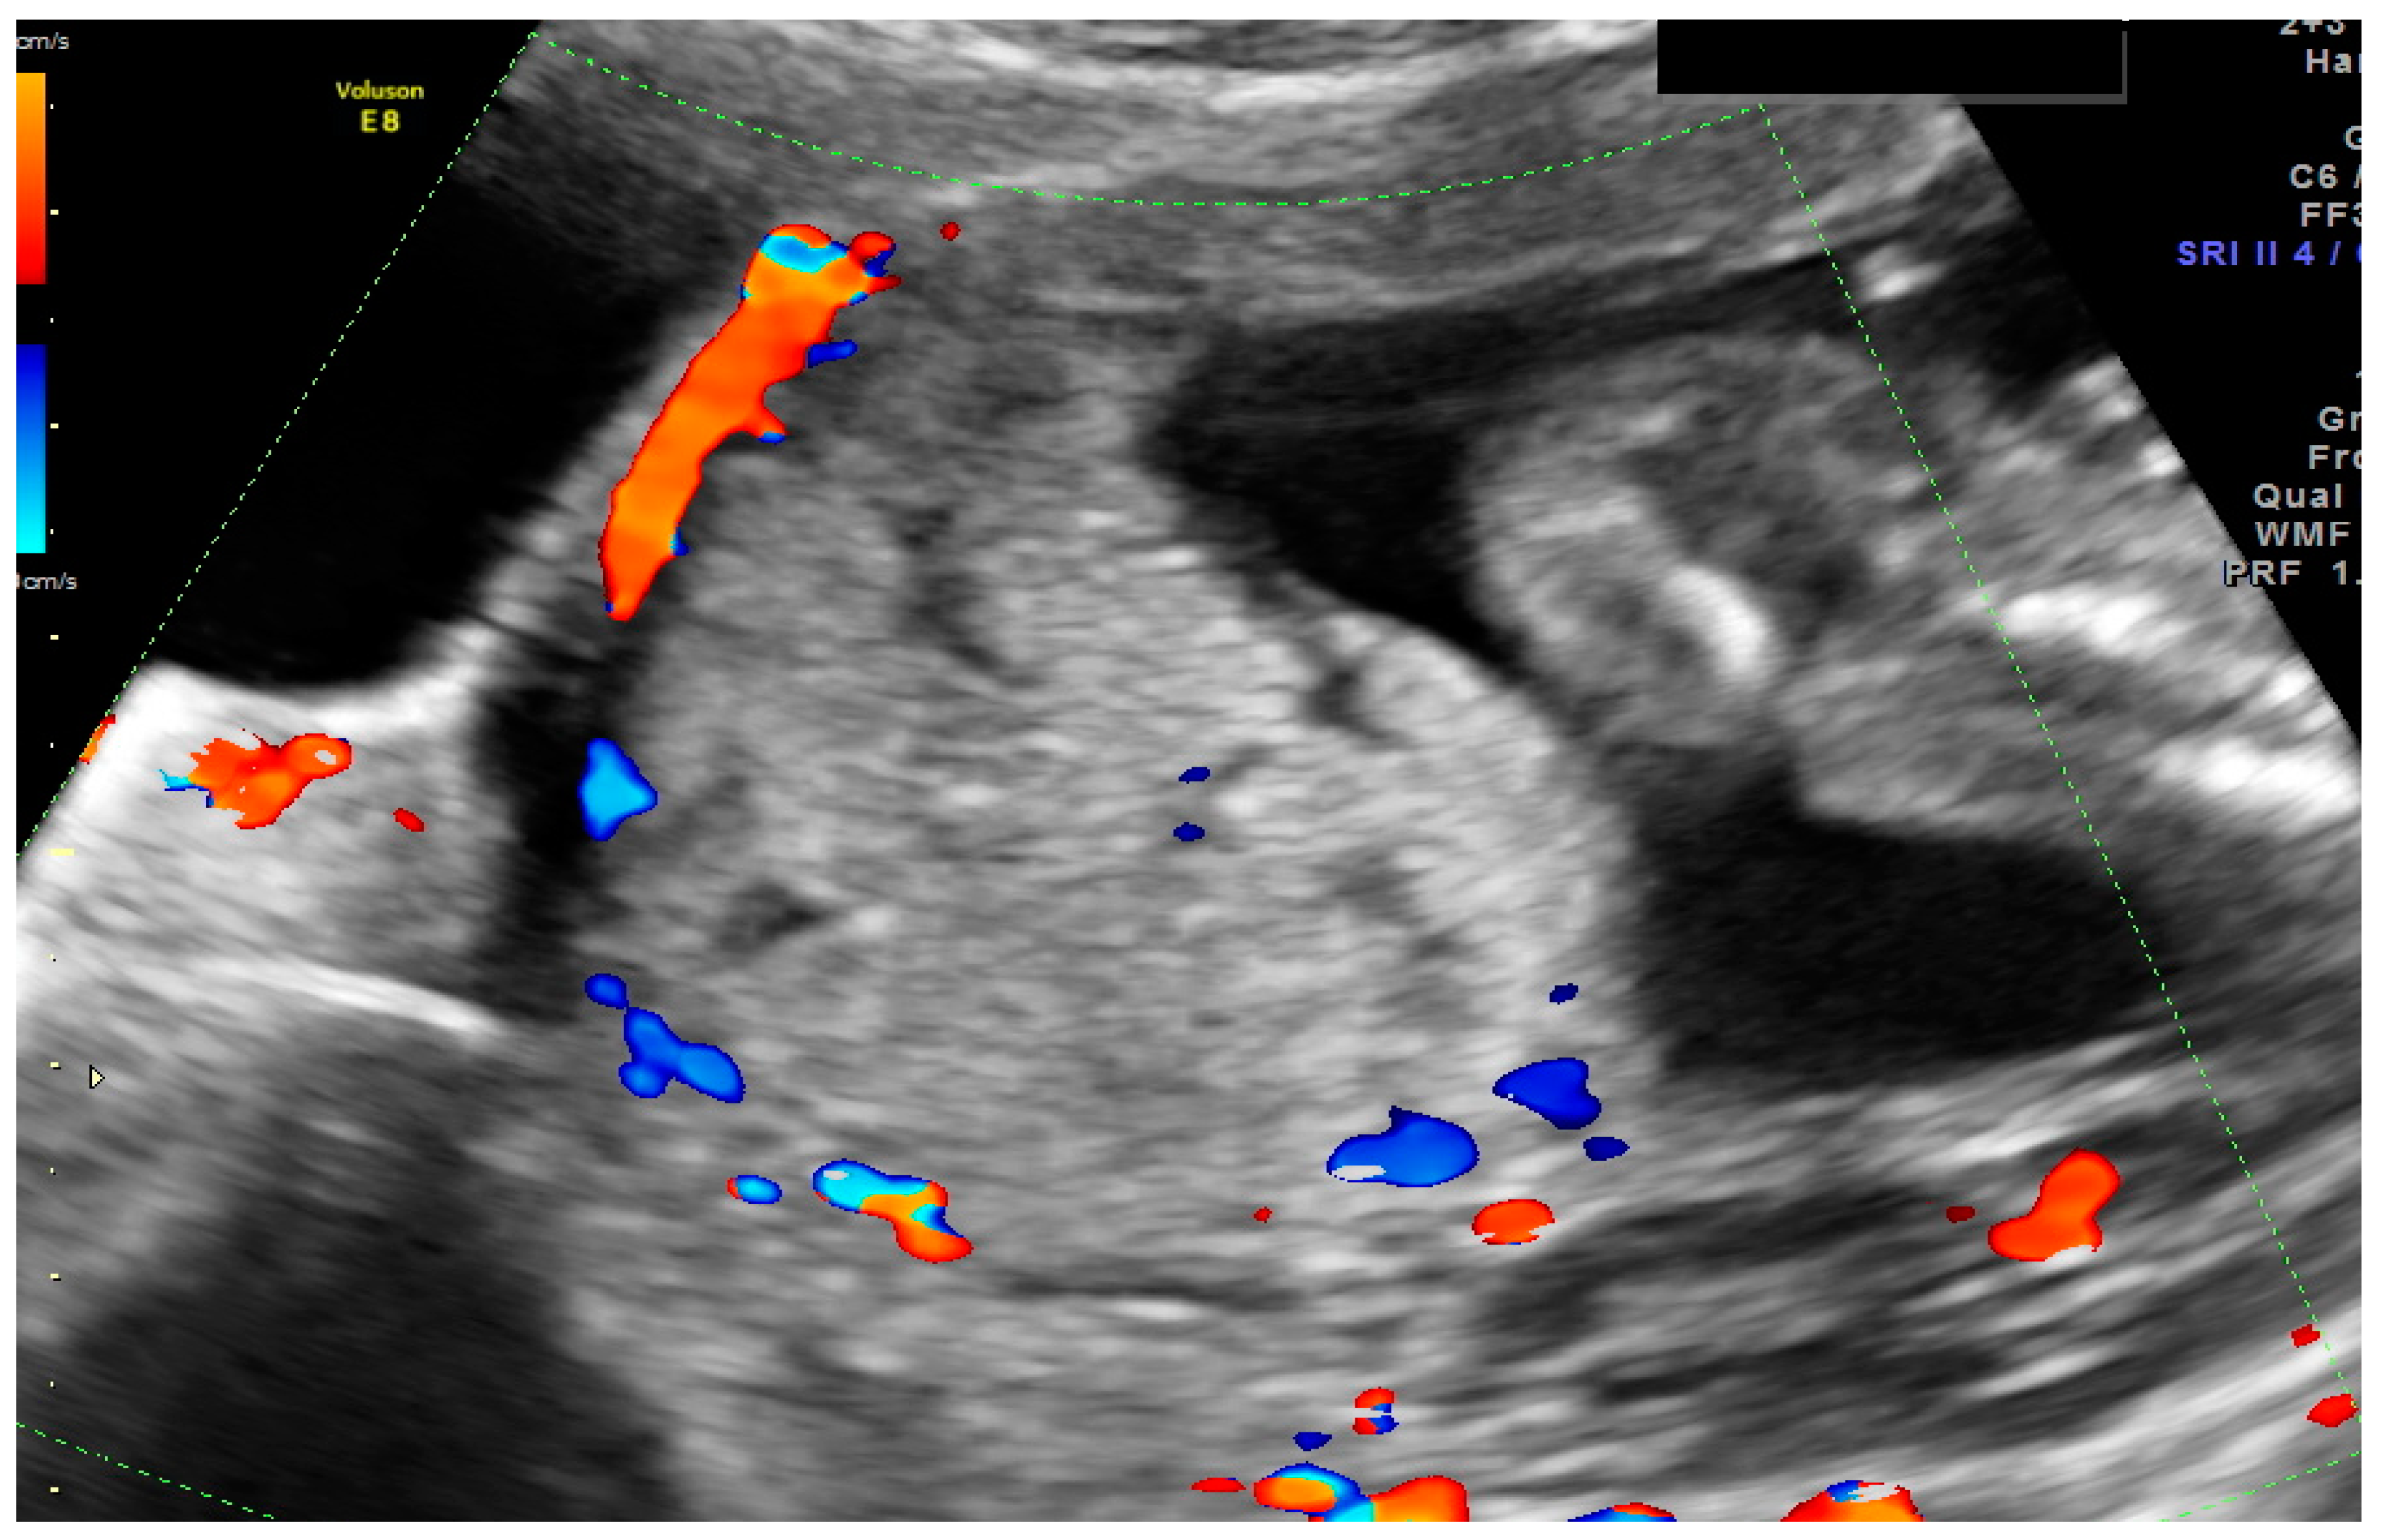

- 1

- an empty uterine cavity with clear endometrium and empty endocervical canal,

- 2

- the detection of a gestational sac within the anterior lower segment of the uterus embedded in the cesarean scar,

- 3

- an absent or thin (<5 mm) myometrium layer between the gestational sac and the bladder,

- 4

- 5

- the pathologies of the adnexa should be excluded, and there should be no detection of fluid in the Douglas pouch unless in the case of a massive hemorrhage or rupture of the uterus [5].

1.1. Case 1